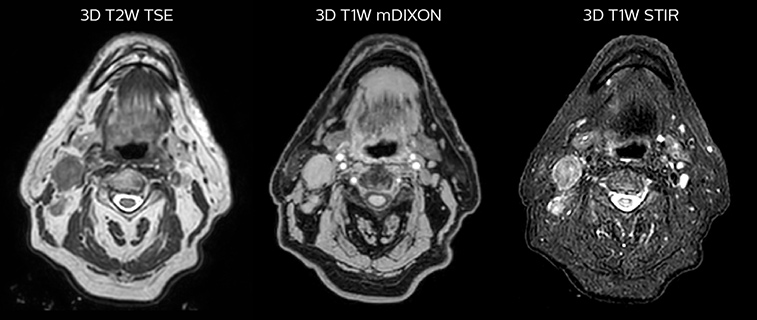

Prostate MR-only radiotherapy planning with use of rectal spacer

Hôpital de La Tour uses an implanted rectal spacer (SpaceOAR®, Boston Scientific) for patients receiving prostate radiotherapy to provide space between the rectum and prostate. 3D T2W TSE MRI provides excellent rectal spacer visualization and is used for OAR and target contouring. The dose plan is calculated on the MRCAT dataset.

Simulation imaging

Tranversal 3D T2W TSE with Compressed SENSE, acquired on Ingenia MR-RT 1.5T (left).

On-console generated MRCAT (right).

MR-based contouring and planning

MRCAT is primary image dataset for dose calculation (left).

3D T2W TSE MRI with 36 cm Field-of-View is used for delineation of prostate and organs at risk (right).